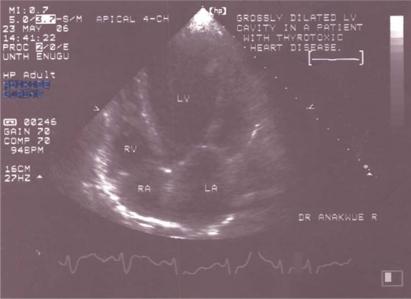

To determine the hospital prevalence, clinical characteristics and echocardiographic findings in patients with thyrotoxicosis who present with congestive heart failure (CCF) in the eastern part of Nigeria.

A total of 50 subjects aged 15 years and above who were diagnosed as thyrotoxic following clinical and thyroid function tests were consecutively recruited. Fifty age- and sex-matched controls with no clinical or biochemical evidence of thyrotoxicosis and no comorbidities were used as controls. Two-dimensional echocardiography was carried out on all the subjects. CCF was determined clinically and echocardiographically.

Eight patients (5 females and 3 males) out of a total of 50 thyrotoxic patients presented with congestive heart failure.

确定尼日利亚东部出现充血性心力衰竭(CCF)的甲状腺毒症患者的医院患病率、临床特征及超声心动图表现。

连续招募了50名年龄在15岁及以上、经临床及甲状腺功能检查确诊为甲状腺毒症的患者。选取50名年龄和性别匹配、无甲状腺毒症临床或生化证据且无合并症的对照者作为对照组。对所有受试者进行二维超声心动图检查。通过临床及超声心动图确定CCF。

50名甲状腺毒症患者中,有8名(5名女性和3名男性)出现充血性心力衰竭。